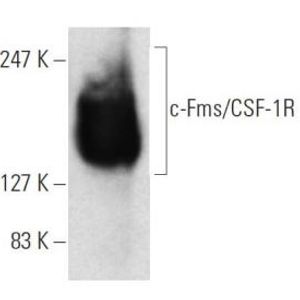

JAN 11, 2021ImmunologyMacrophages are a type of immune cell that can detect and destruct bacteria, viruses, and harmful materials. They a ...